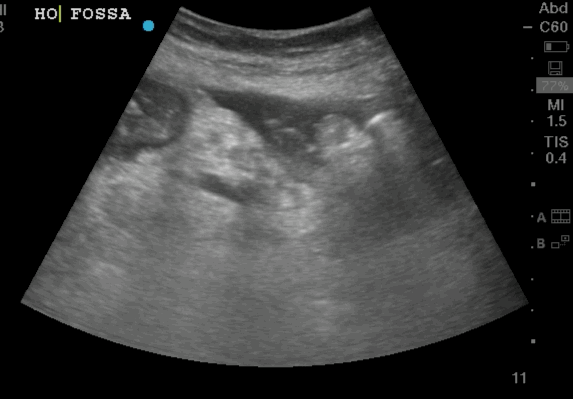

- The focused questions:

- Is free fluid present between the intestines loops

The video clip shows a small rim of free fluid along the liver edge with extensive free fluid noted amongst the intestinal loops

Free Fluid Around the Intestinal loops